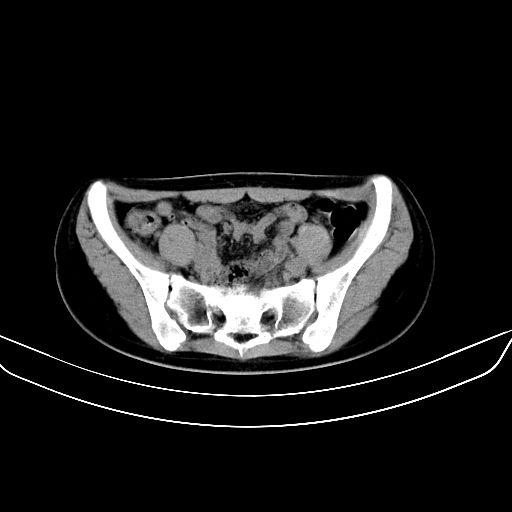

以下是引用zsl6918在2008-7-11 21:40:00的发言:[br]双侧骶髂关节骨质破坏以下三分之一为主,符合强直性脊柱炎表现

以下是引用zhangzhongshou在2008-7-11 21:41:00的发言:[br]患者是女性,hla-b27抗原(—),首先不太考虑强直性脊柱炎,建议查类风湿因子,骶髂关节改变考虑类风湿性关节炎可能性大,建议进一步检查。